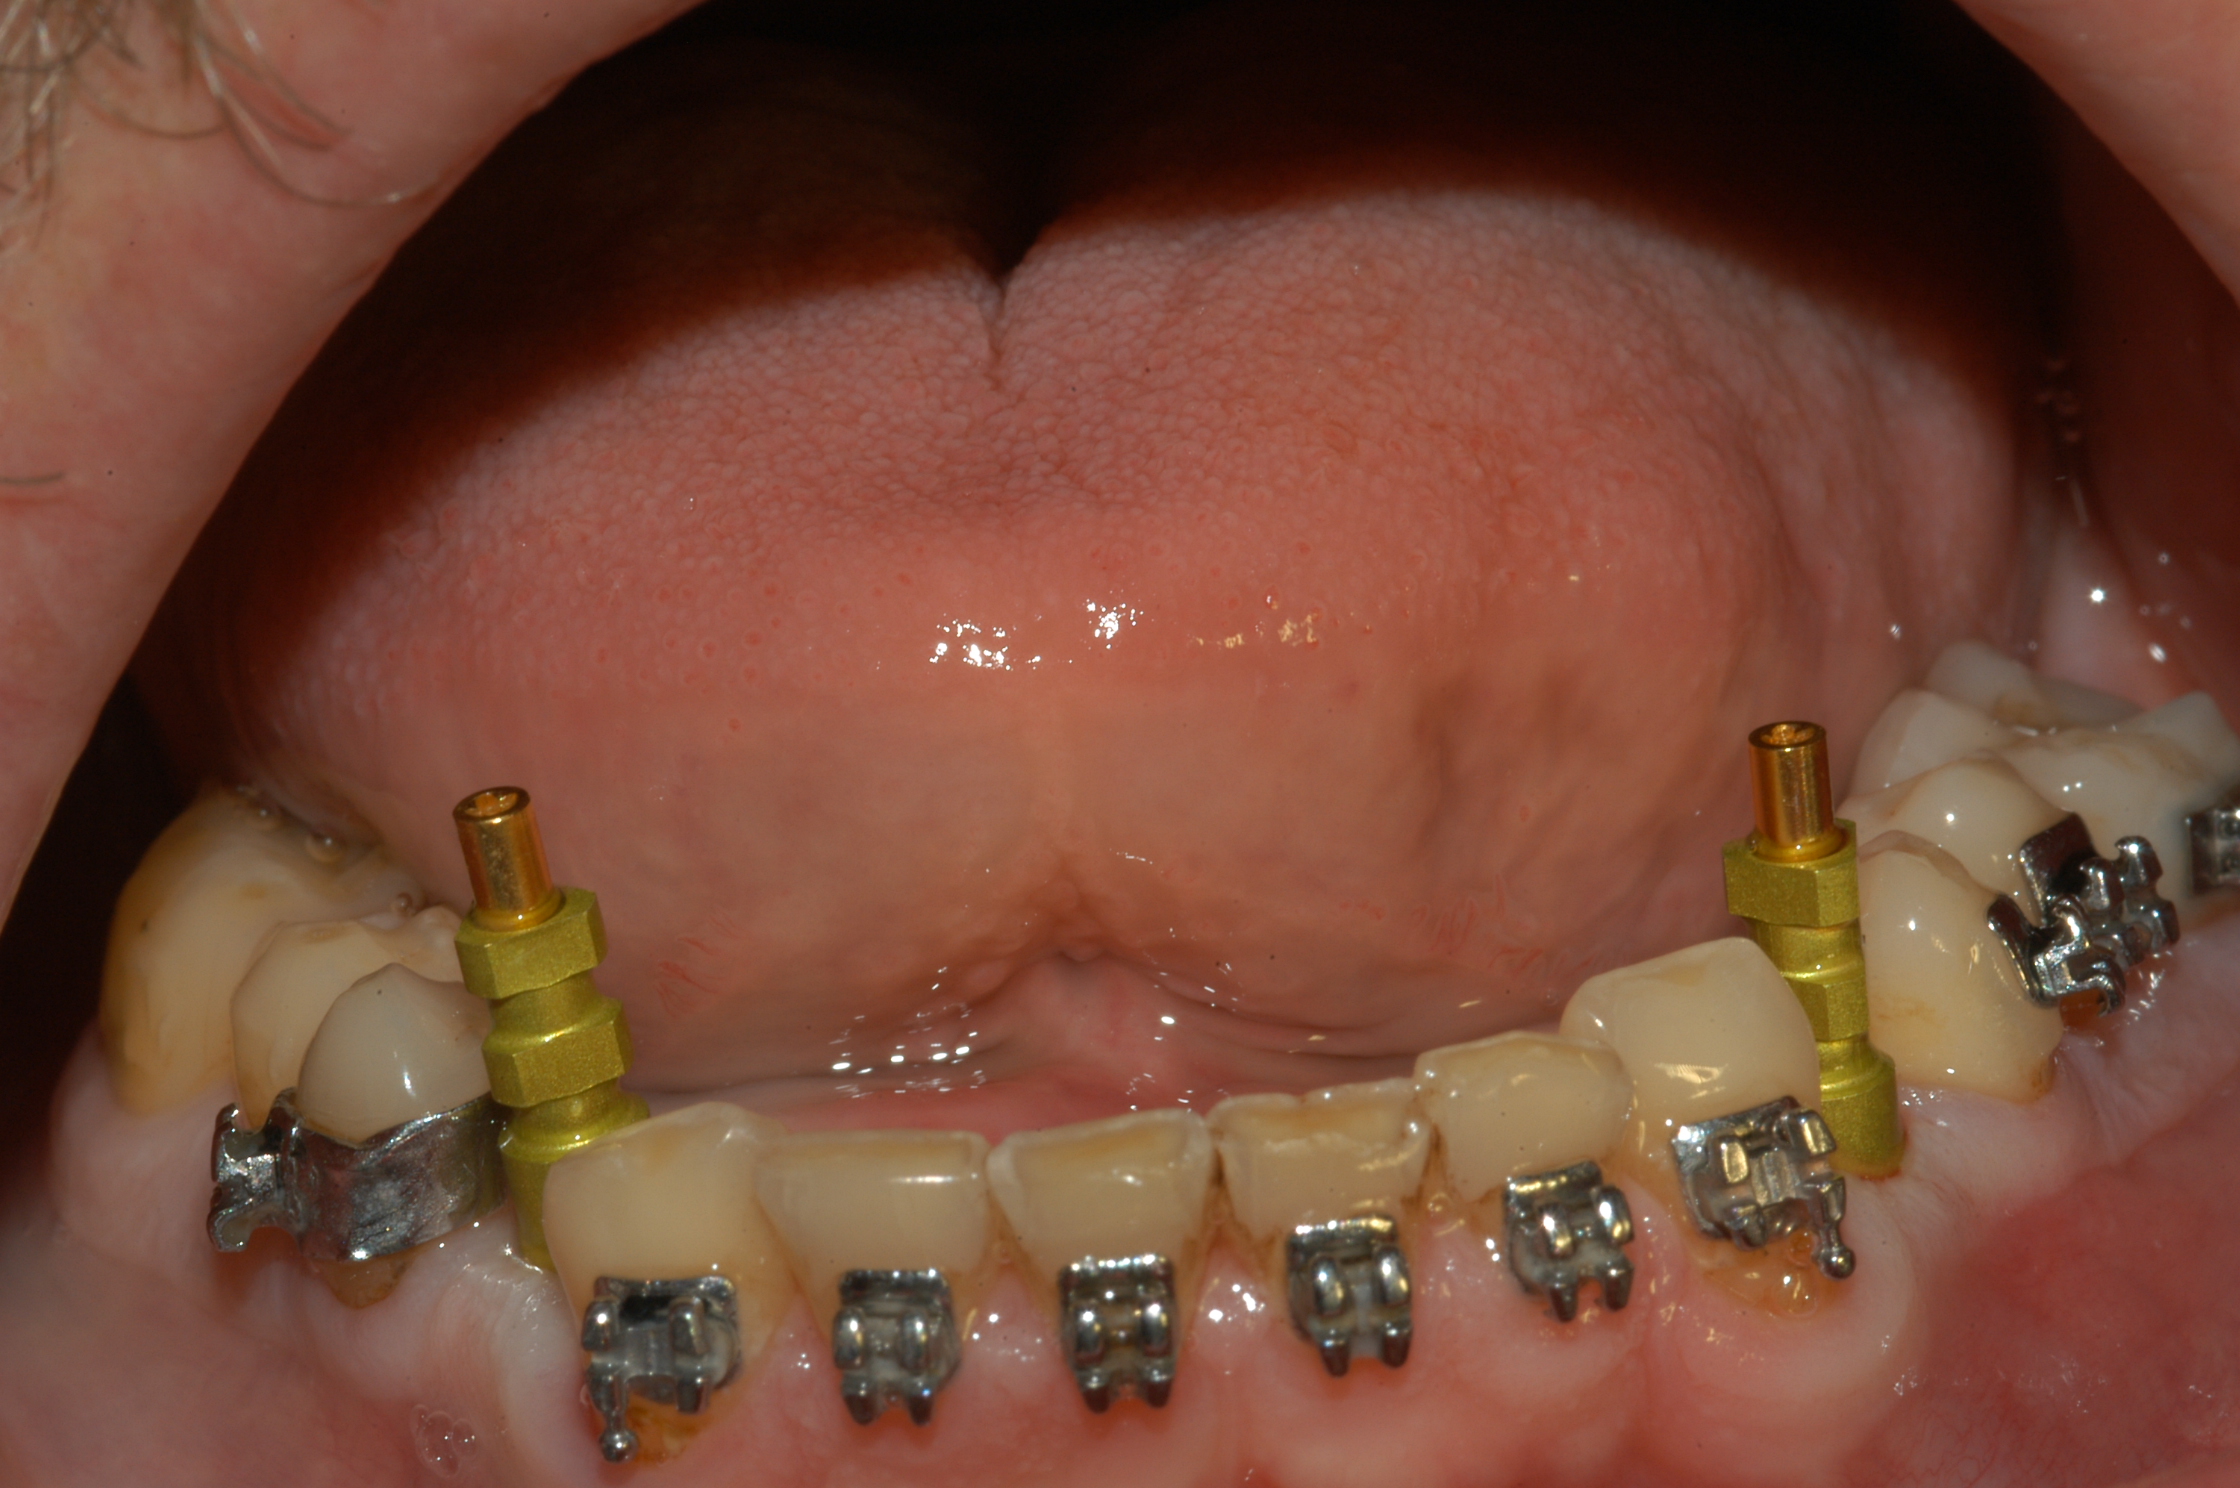

Progettazione virtuale / chirurgia guidata Un esempio della progettazione 3D di un intervento di posizionamento implantare SENZA BISTURI. Photogallery: